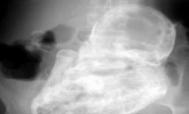

3.骨折

是退行性骨质疏松症最常见和最严重的并发症。